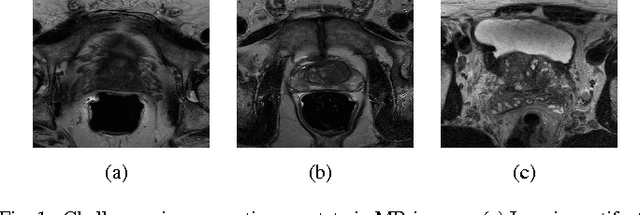

Prostate segmentation from Magnetic Resonance (MR) images plays an important role in image guided interven- tion. However, the lack of clear boundary specifically at the apex and base, and huge variation of shape and texture between the images from different patients make the task very challenging. To overcome these problems, in this paper, we propose a deeply supervised convolutional neural network (CNN) utilizing the convolutional information to accurately segment the prostate from MR images. The proposed model can effectively detect the prostate region with additional deeply supervised layers compared with other approaches. Since some information will be abandoned after convolution, it is necessary to pass the features extracted from early stages to later stages. The experimental results show that significant segmentation accuracy improvement has been achieved by our proposed method compared to other reported approaches.